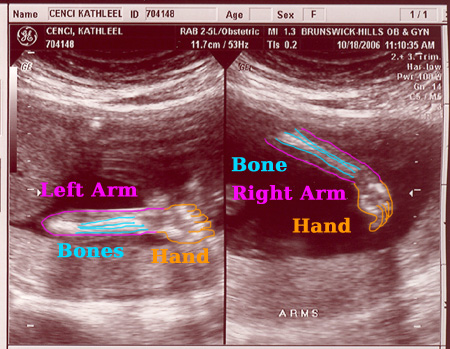

| On October 18, 2006 we had the second sonogram. The baby is growing well. It was moving quite a bit while we were watching. It is amazing to actually see feet, arms, ribs, the spine, we even saw it sucking it's thumb. Check out the photos below. Each one is clickable which will bring you to labeled versions to help you identify what you're looking at. Enjoy! |

Click on any/all of the photos above to see more. The links will give you full resolution photos and labeled versions. The labeling is my best guess as to what your looking at. We saw much more on the monitor, the motion version was awesome.